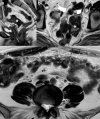

Although rare, uterine sarcoma is a diagnosis that no one wants to miss. Often benign leiomyomas (fibroids) and uterine sarcomas can be differentiated due to the typical low T2 signal intensity contents and well-defined appearances of benign leiomyomas compared to the suspicious appearances of sarcomas presenting as large uterine masses with irregular outlines and intermediate T2 signal intensity together with possible features of secondary spread. The problem is when these benign lesions are atypical causing suspicious imaging features. This article provides a review of the current literature on imaging features of atypical fibroids and uterine sarcomas with an aide-memoire BET1T2ER Check! to help identify key features more suggestive of a uterine sarcoma.